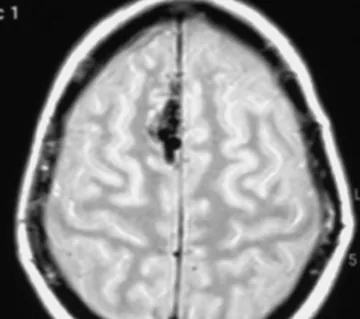

Cerebral angiography, sometimes also called a cerebral arteriogram, provides the most detailed images of a cerebral AVM (fig. 2). This procedure involves threading a catheter (a thin, flexible tube) through an artery in the arm or leg up to the arteries in the head. A contrast agent is then injected through the catheter. As the contrast agent flows through the blood vessels of the brain, a sequence of X-ray images are taken. These images can provide a highly detailed view of the AVM, showing the exact location, size, and the blood flow pattern.

Figure 2: Cerebral angiogram of an AVM located in the occipital lobe (back of the brain).